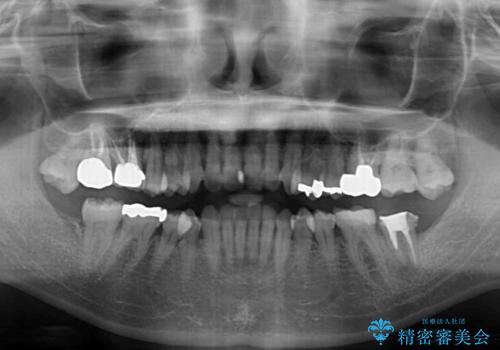

- 上下前歯のデコボコと、奥歯の銀歯を気にして来院された患者様です。

概ね歯列が整ったところで銀歯の全てをセラミッククラウンなどに置き換え、その後インビザラインを1セット使用して仕上げていくこととしました。